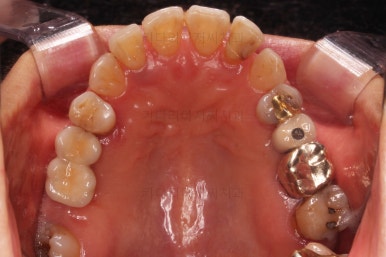

초진 시 입안의 모습입니다.

일반적인 교정을 하기에는 적합한 모습은 아니었어요.

치아는 군데군데 없고 임플란트도 있고 브릿지로 연결된 치아도 있으며 전반적인 잇몸 상태도 좋지 못했어요.

앞니가 벌어져 있고 뻗쳐 있으며 잇몸에서 쏙 빠져나와 있는 듯한 느낌이었어요.